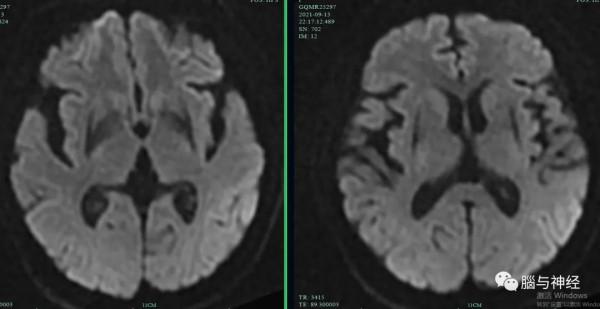

先看影像,可見殼核萎縮、外緣裂隙徵。

最典型還是SWI,類似尿毒症或糖尿病酸中毒的“叉徵”,可稱作“黑色叉徵”。殼核外緣的裂隙徵更明顯。

一是影像典型:殼核改變,包括殼核萎縮、殼核背外側低訊號、殼核外緣的裂隙徵都很有特點。不僅傳統的T2相,可以看出SWI、DWI和ADC圖對於殼核異常也很有診斷價值。請看文獻報道的DWI、ADC圖和SWI對MSA的診斷價值。